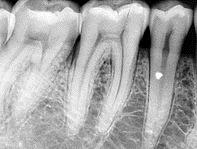

Визиография ― новый метод диагностики заболеваний полости рта, контроля за процессом лечения посредством современного цифрового оборудования ― визиографа. Специальный датчик передает изображение не на пленку, а на компьютер, где оно может обрабатываться и храниться.

Еще несколько лет назад подобные снимки делались на пленку, изображение на которой во многих случаях не позволяло врачу объективно оценить эффективность лечебных процедур. Сегодня в снимок выполняется с помощь визиографа – цифрового рентгенологического аппарата, способного выявить мельчайшие дефекты и поражения структуры зуба или десны. Зачастую увидеть причину воспаления или острой боли можно только на рентгеновском снимке.

Четкость изображения: благодаря высокому разрешению качество снимков на визиографе намного выше, что позволяет видеть все нюансы изменения в тканях ротовой полости в ходе лечения.

Информативность: возможность работы стоматолога с изображением на мониторе компьютера, увеличивая картинку, выделяя рельеф, а также проводить необходимые математические расчеты, определяя плотность тканей кости и зуба или размеры.